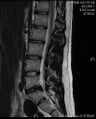

- التصوير بالرنين المغناطيسي هي الدراسة المعيارية الذهبية لتأكيد الاشتباه في انزلاق غضروفي. مع دقة تشخيصية تبلغ 97%، فهي الدراسة الأكثر حساسية لتصور الانزلاق الغضروفي بسبب قدرتها الكبيرة على تصور الأنسجة الرخوة. كما يتمتع التصوير بالرنين المغناطيسي بموثوقية أعلى بين المراقبين مقارنة بوسائل التصوير الأخرى. ويشير إلى انزلاق غضروفي عندما يظهر إشارة متزايدة مرجحة بـ T2 عند المنطقة الخلفية التي تغطي 10% من القرص. وقد أظهرت أمراض الانزلاق الغضروفي ارتباطًا بتغيرات النوع 1 من مقياس موديك. عند تقييم اعتلالات الجذور العصبية القطنية بعد الجراحة، فإن التوصية هي إجراء التصوير بالرنين المغناطيسي مع التباين ما لم يكن هناك موانع أخرى. يعد التصوير بالرنين المغناطيسي أكثر فعالية من التصوير المقطعي المحوسب في التمييز بين الأسباب الالتهابية أو الخبيثة للانزلاق الغضروفي. يُشار إليه في وقت مبكر نسبيًا في مسار التقييم (<8 أسابيع) عندما يظهر المريض مؤشرات نسبية مثل الألم الشديد والعجز الحركي العصبي ومتلازمة ذيل الفرس. التصوير الموتر الانتشاري هو نوع من تسلسل التصوير بالرنين المغناطيسي المستخدم للكشف عن التغيرات الدقيقة في جذر العصب. قد يكون مفيدًا في فهم التغييرات التي تحدث بعد أن يضغط القرص القطني المنفتق على جذر العصب، وقد يساعد في التمييز بين المرضى الذين يحتاجون إلى تدخل جراحي. في المرضى الذين لديهم شكوك عالية في اعتلال الجذور العصبية بسبب الانزلاق الغضروفي القطني، ومع ذلك فإن التصوير بالرنين المغناطيسي غامض أو سلبي، يوصى بدراسات التوصيل العصبي.[44] توفر الصور المرجحة الناتجة عن التصوير بالرنين المغناطيسي (T2) تصور واضح لمادة القرص البارز في القناة الشوكية.

مثال على انزلاق غضروفي في الفقرات القطنية الخامسة والعجزية الأولى في العمود الفقري القطني.